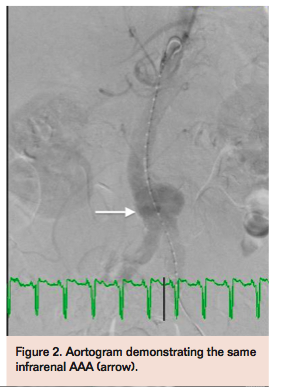

The patient was brought to the catheterization laboratory, prepped, and draped in sterile fashion for percutaneous access. Micropuncture access was obtained in bilateral femoral arteries with placement of 6 Fr sheaths bilaterally. Selective angiograms confirmed common femoral artery access with minimal disease and a Prostar XL Percutaneous Vascular Surgical device (Abbott Vascular) was predeployed to deliver sutures at each puncture site for hemostasis at completion of the procedure. Descending aortogram confirmed a distal AAA with a long infrarenal neck (Figure 2). Intravascular ultrasound imaging (IVUS) corroborated findings (Figure 3) from the CT angiogram and aortogram. An Ovation 26 mm aortic body stent graft (TriVascular) was selected due to the low-caliber 14 Fr outer diameter of this device, and advanced sheathless via the right femoral artery.